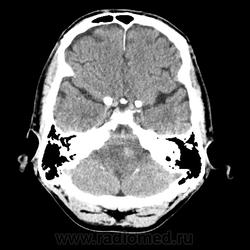

КТ ГМ+C Субтенториальное объемное образование в стволе головного мозга (мост)

Мужчина 46 лет. Поступил с подозрением на ОНМК. Жалобы на шаткую походку, снижение зрения. Мост содержит ядра ЧМН (V, VI, VII, VIII). Для невриномы и менингиомы не  характерна локализация. Узловое, экспансивно растущее образование, интенсивно накапливает КВ. DDs: Кавернозная ангиома, mts.

Ну да, перифокального отека нет, лишь IV желудочек компремирован. МРТ точно рассудит.

Да как то не выражен, может незначительный, IV желудочек не резко  деформирован и сужен.

По-моему отека предостаточно.

мост и левая средняя мозжечковая ножка гипо-, цистерн ЗЧЯ вообще не видно...